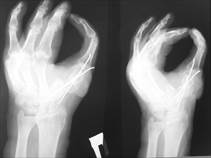

Восстановление пястных костей

Восстановление пястных костей 140 фотографий